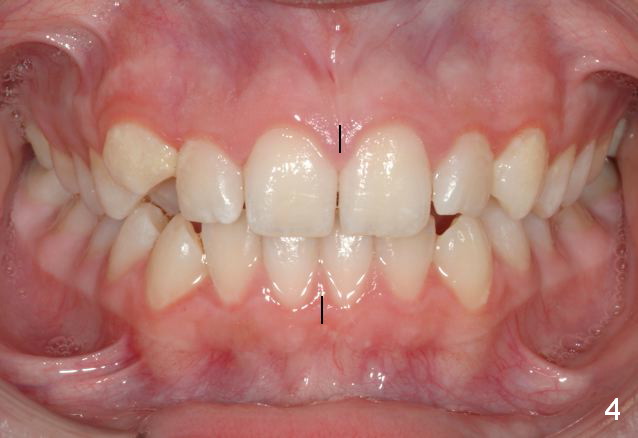

Unilateral Class II Malocclusion

The upper dental midline deviates to the left (Fig.2,4). Facial profile is normal (Fig.3). The right molar relationship is Class II (Fig.5), while the left one is normal or slightly Class III (Fig.6). How to treat?